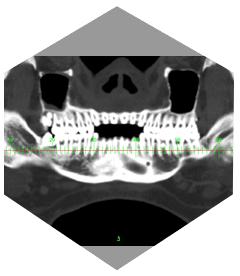

• Bietet Kunden einen 128-Zeilen-CT mit einer großen 76 cm Apertur

und verbessert die Bildauflösung auf 21 Lp/cm, was zu einer

genauen Krankheitsdiagnose und -behandlung beiträgt und

die klinische Leistungsfähigkeit und Erweiterbarkeit des Geräts erheblich verbessert.